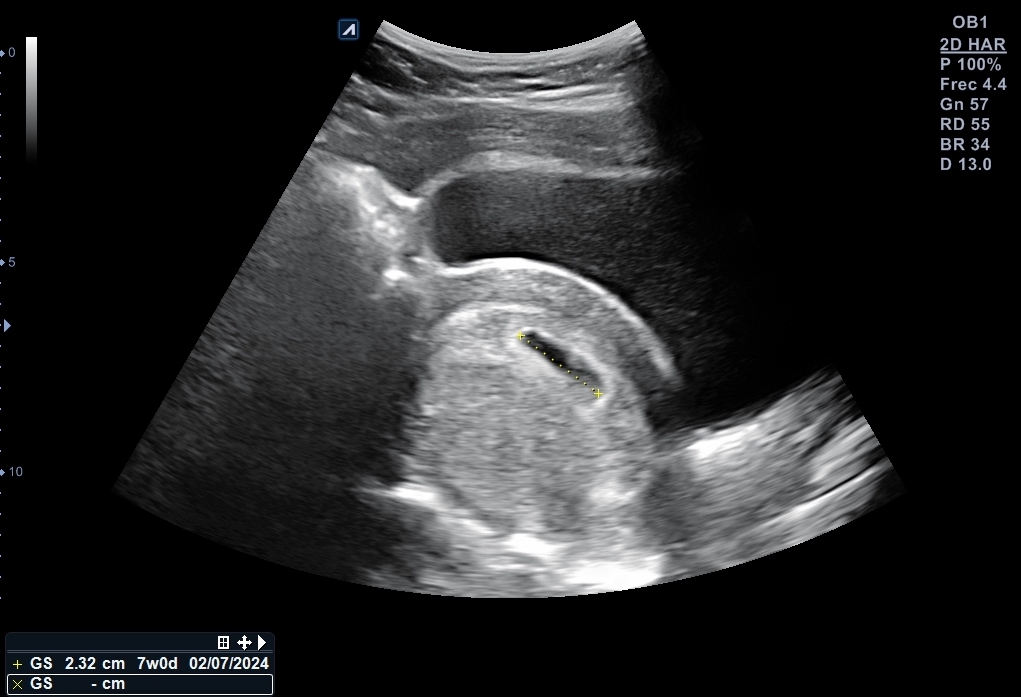

Se explora pelvis con sonda cónvex: vejiga distendida de paredes lisas y homogéneas. Útero en anteversión con endometrio decidualizado y saco embrionario en su interior, bien posicionado con una estimación de 6 + 2 semanas de gestación. Se localiza cuerpo lúteo en anejo izquierdo que, además está aumentado de tamaño.